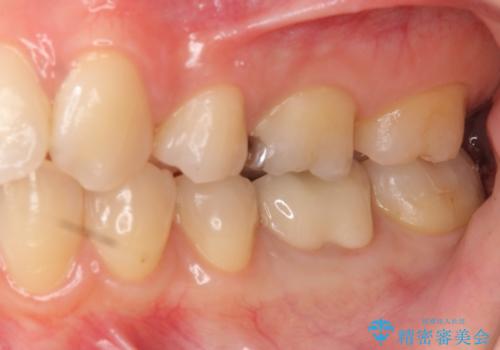

ただし、元のインレーが遠心マージンが縁下だったため、矯正治療後に歯ぐきの厚みを減らして、しっかり歯ぐきの上にマージンラインが来るように整える手術(ディスタルウェッジ)を行いました。

手術後、きちんとマージンラインが歯肉の上に来た状態で、セラミックインレー修復を行いました。

レーザーや電気メスで分厚い歯肉を焼いても一時的で、やがてまた元のように歯ぐきが上まで増殖しますので、今回は骨の厚みも調整し、7番の遠心を出来るだけ下げました。